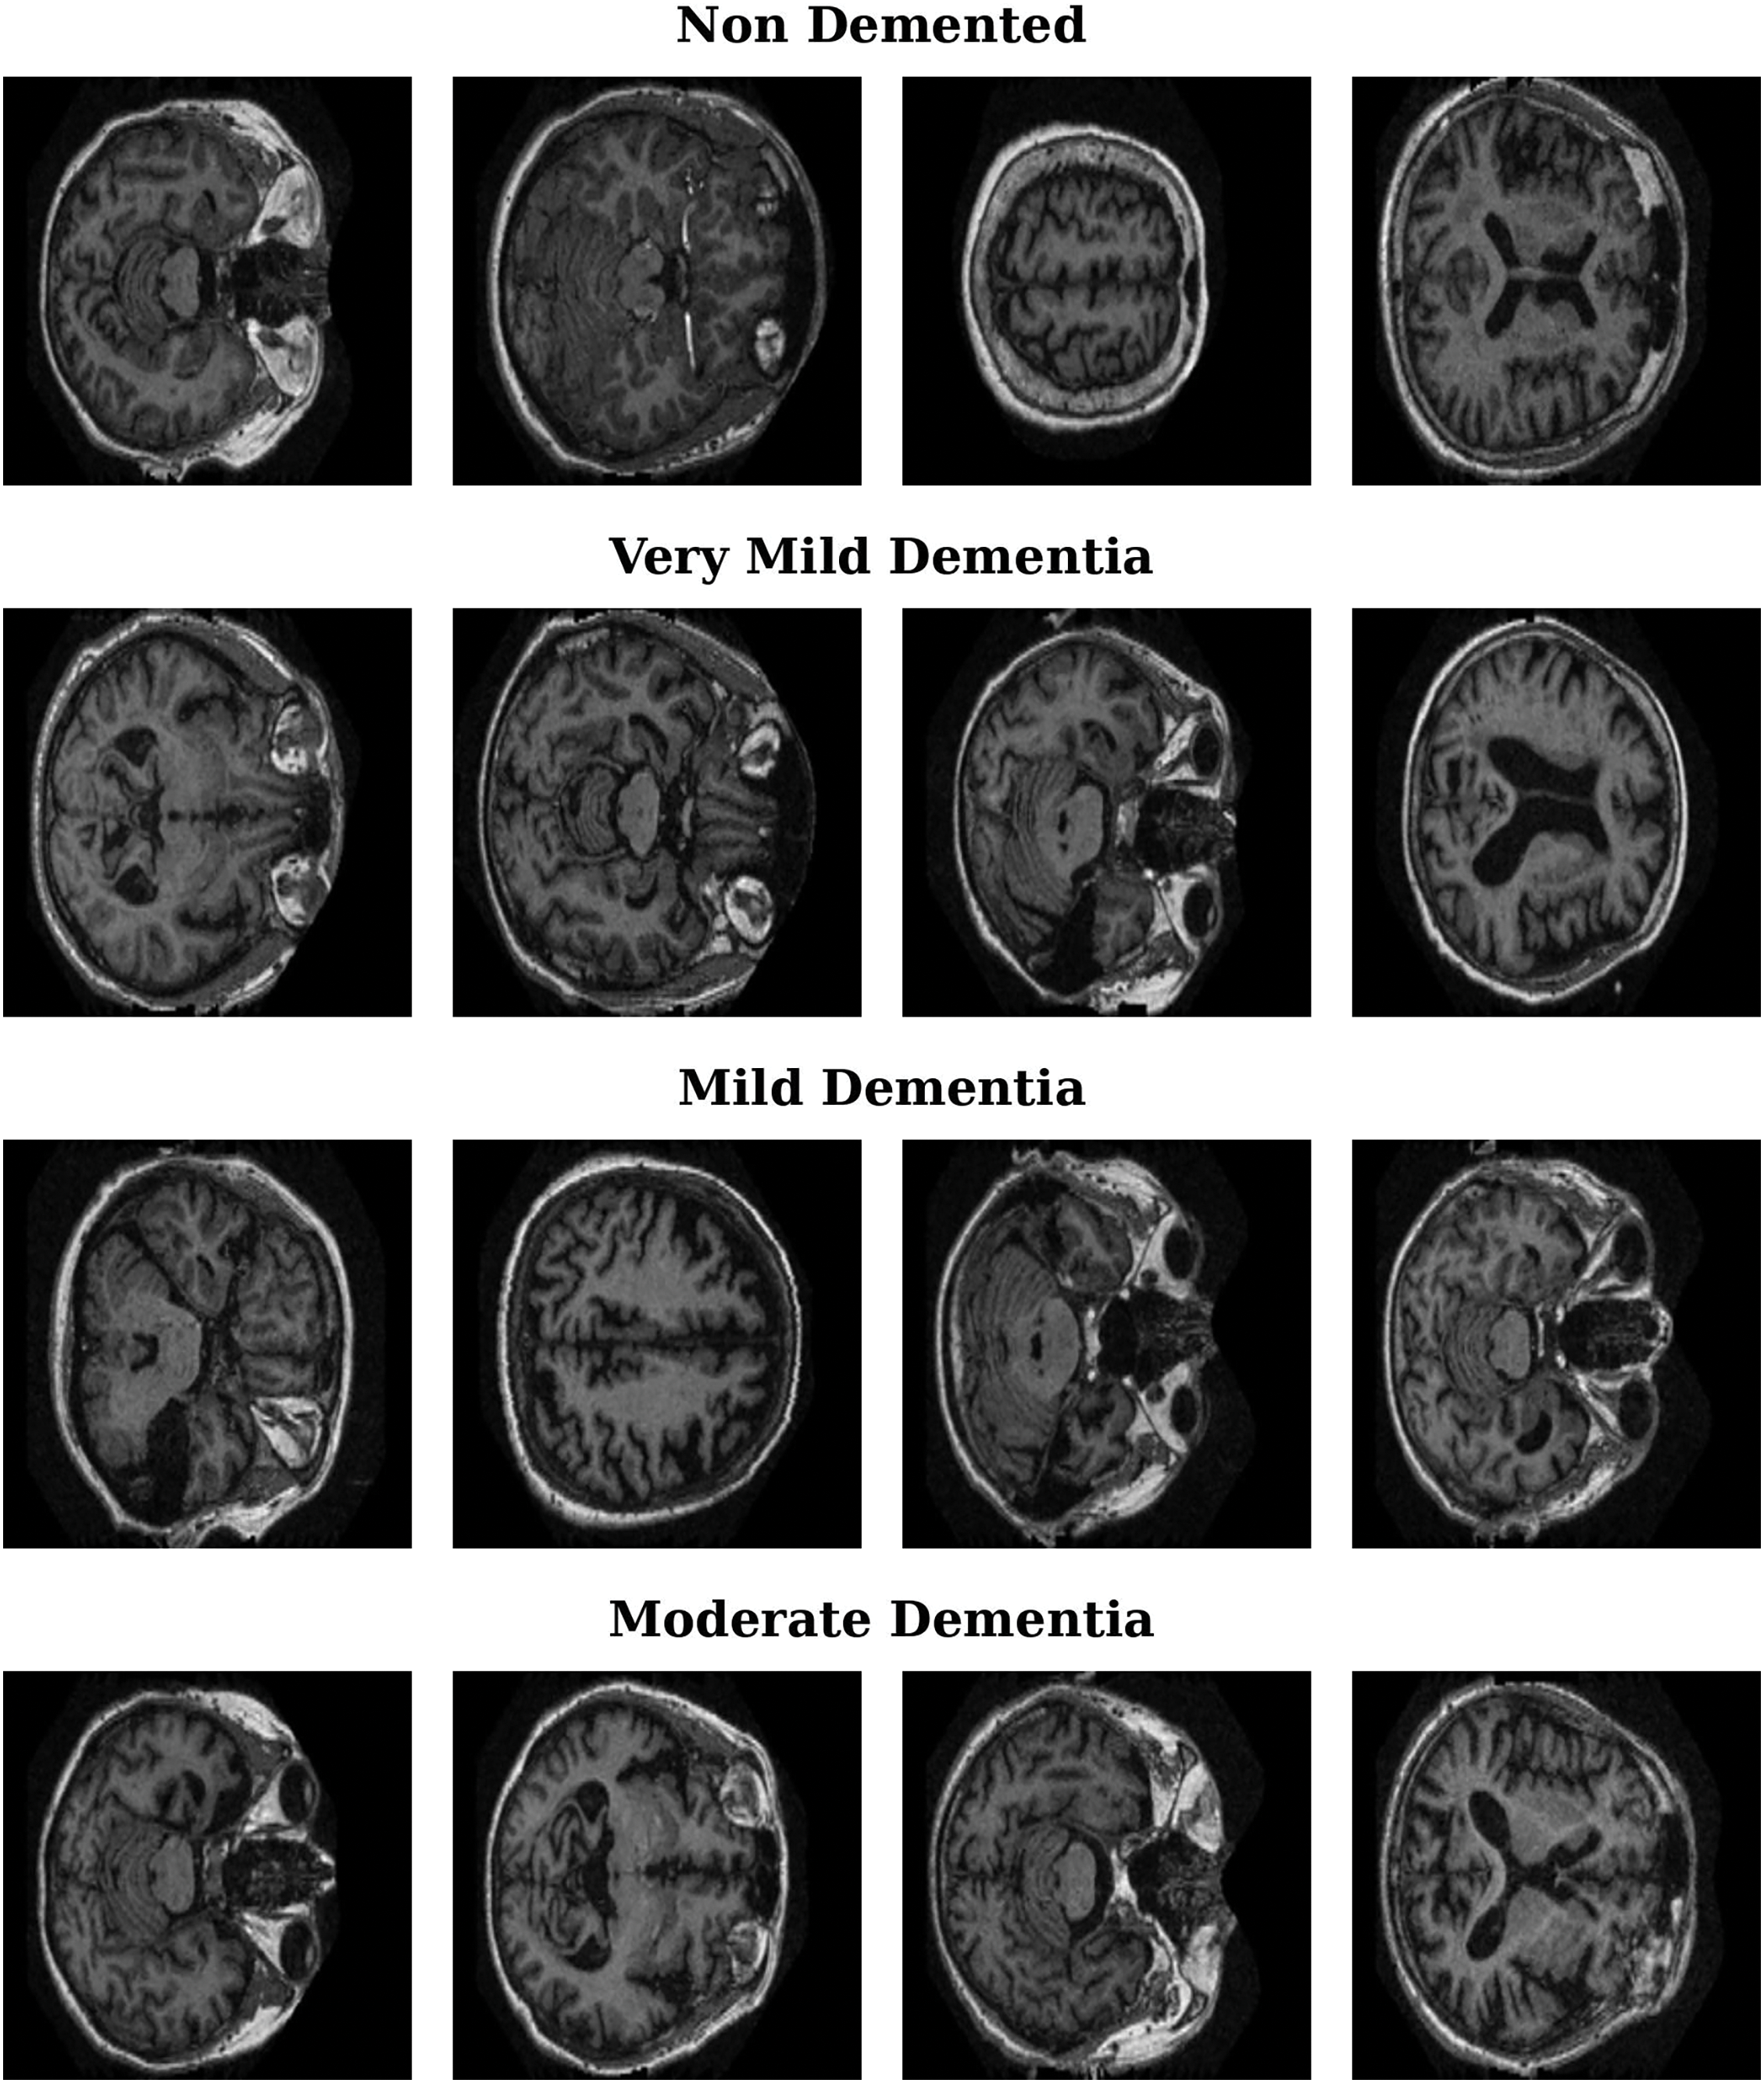

The OASIS MRI dataset [35–38] used in this study contains more than 80,000 brain MR images categorized into four classes on the basis of AD progression: moderate dementia, very mild dementia, mild dementia, and nondemented. These images were obtained from 461 patients, offering a robust dataset for AD detection and analysis. Patient classification was based on clinical dementia rating (CDR) values, resulting in four distinct classes, as shown in Table 1. This classification enables the study of AD progression across different stages. Fig. 1 presents sample MRI images from the dataset, showcasing representative examples from each of the four categories. These samples highlight the visual differences and subtle patterns associated with each stage of AD progression.

Figure 1: Representative MRI images for Alzheimer’s disease stages